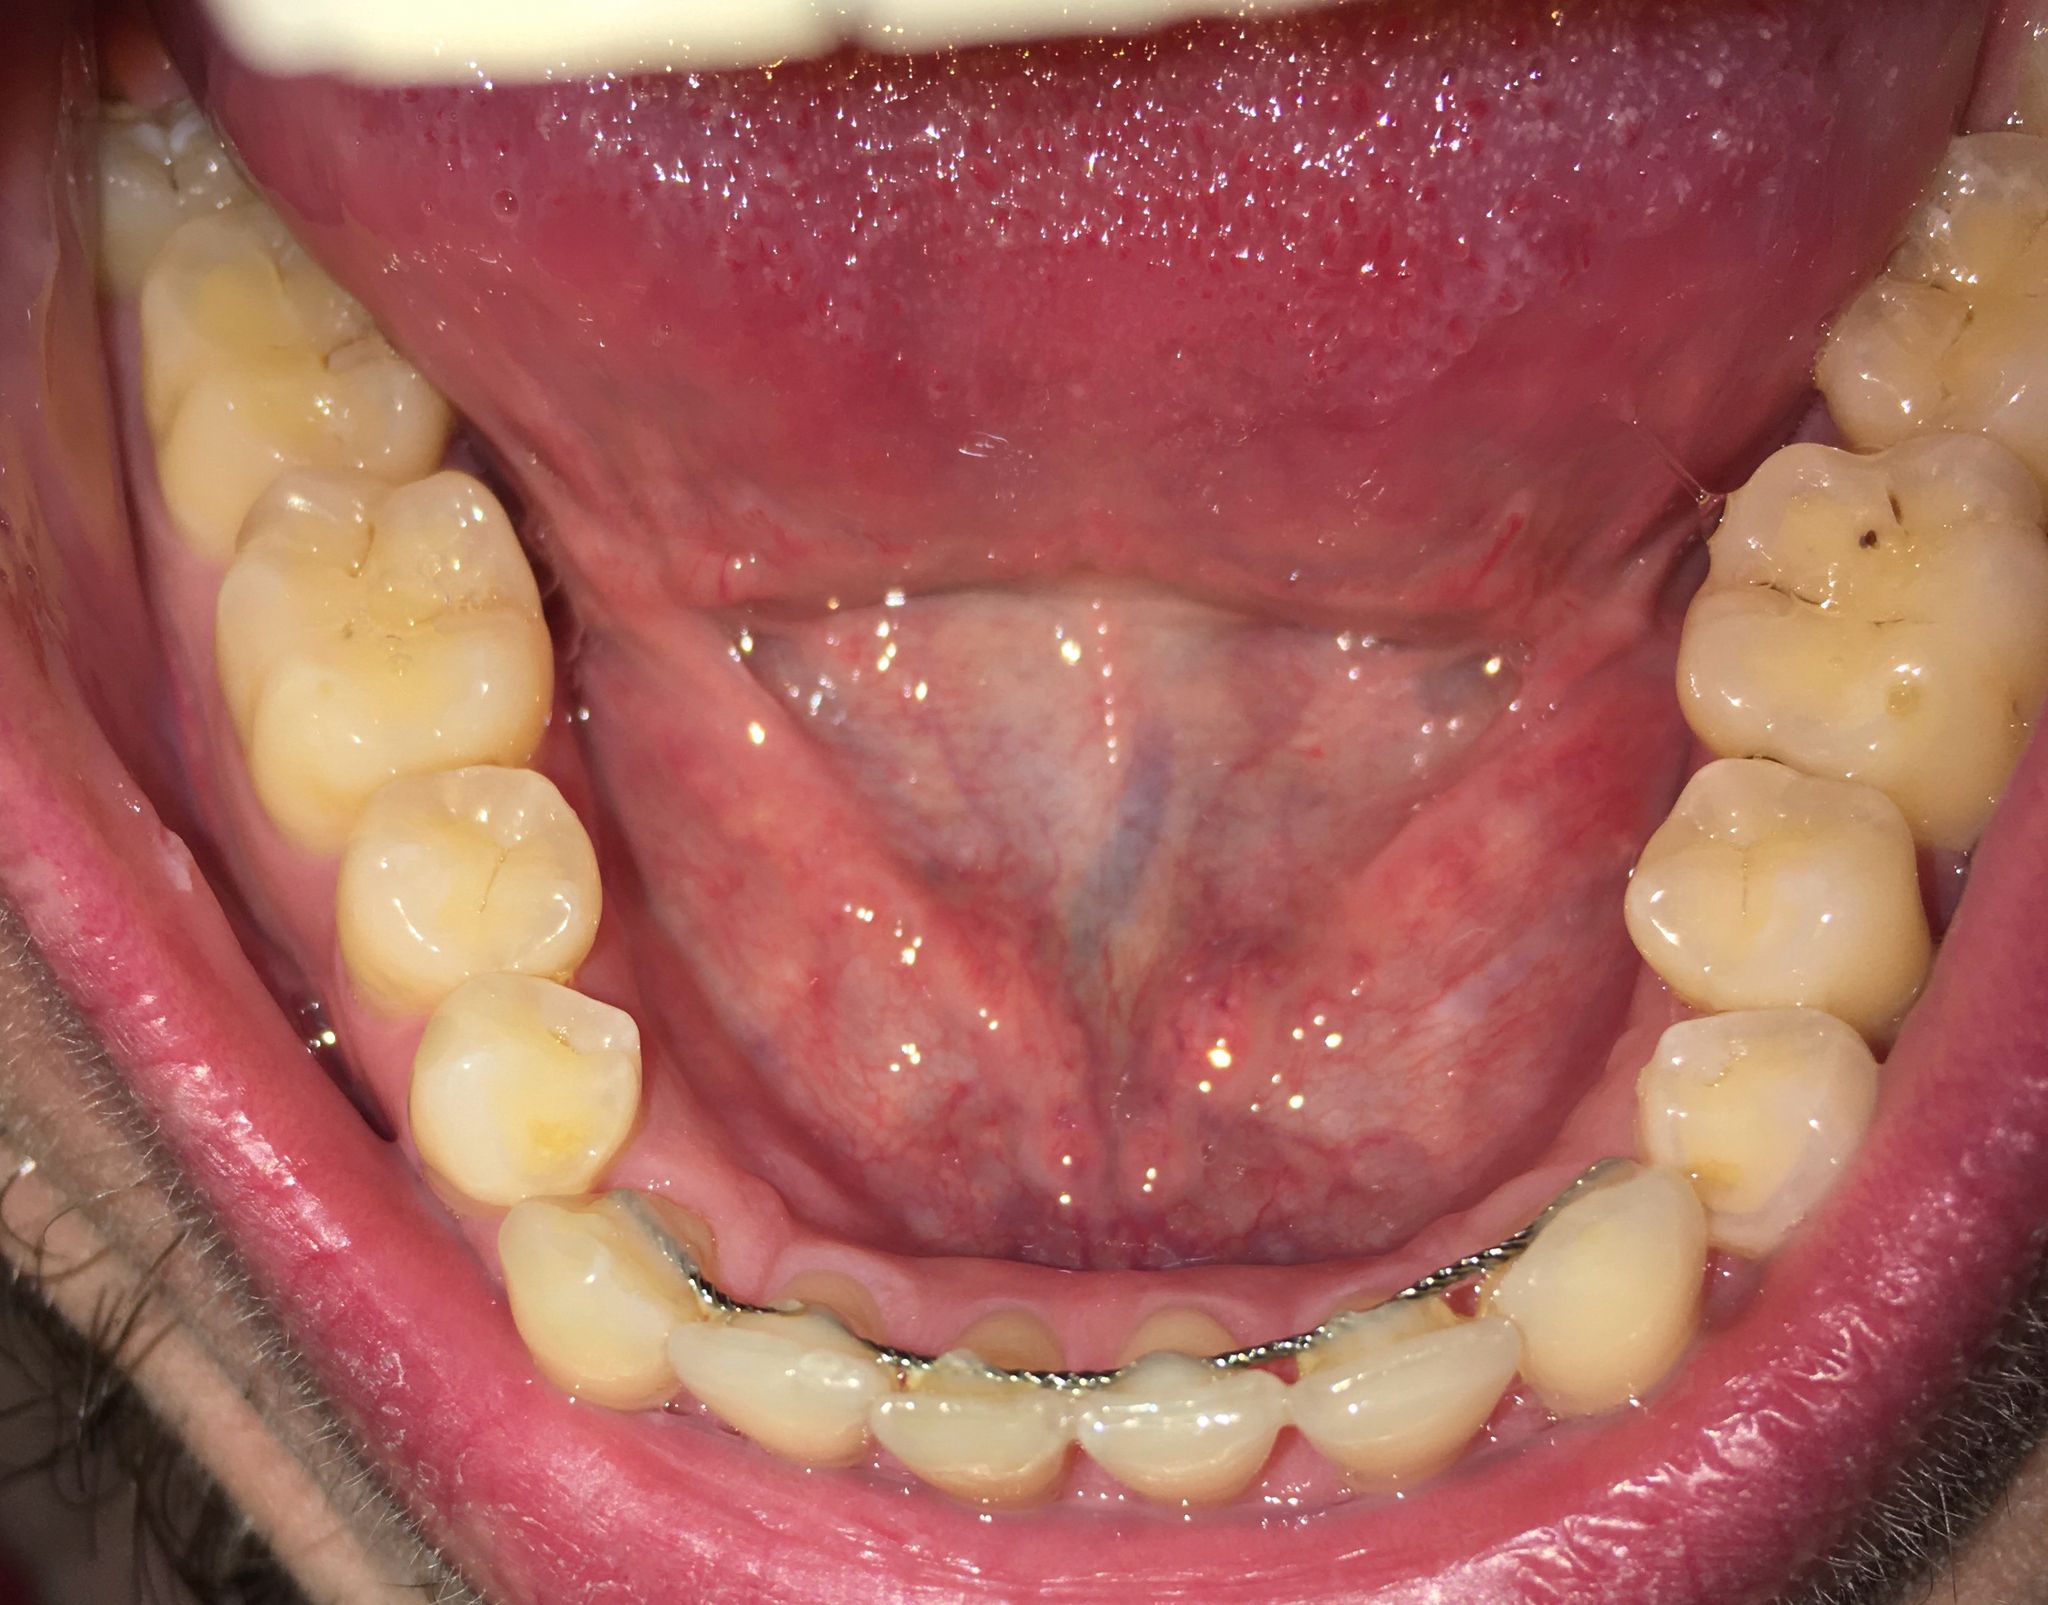

Ik had in april dit jaar al een vraag gesteld in dit forum over mijn mogelijke erosie, u gaf toen aan dat er enige slijtage was. Ik heb totaal geen idee hoe het kan zijn ontstaan, omdat ik mijn hele leven al zowat geen suikers of prik of zure dranken nuttig. Mijn tandartsen en mondhygienisten hebben er ook NOOIT wat over gezegd. Hierbij een foto van 2015 en 2025 onderkaak tanden. Ik zie in die 10 jaar geen verschil. Is het echt flinke slijtage of valt het mee? Wat betreft mijn botniveau, heb ik inderdaad te horen gekregen dat er sprake is van lichte botafbraak, ik gebruik nu elke dag ragers. Heb in het verleden ook een beugel gehad, zou dat ook voor veranderingen in het bot kunnen zorgen? x-fotos van mijn rechter kaak uit 2010 en eind 2024.

Op grond v deze foto's moeilijk te zeggen maar lijkt meer.

Bovenste x-foto lijkt meer dan onderste foto maar kan ook aan de inschiet richting liggen.

Lijkt de erosie meer te zijn bedoel je? de tweede foto is iets warmer dan de eerste omdat het twee verschillende camera's zijn, maar ik zie persoonlijk geen verschil, hoop dat het in ieder geval gestopt is. En wat betreft de x-foto's, de tweede is recent en de eerste is van 14 jaar geleden. En wat betreft mijn pericoronitis, pijn is volledig weg, maar het tandvlees daar is nog zacht en niet strak tegen de verstandskies aan. Is dit een probleem en gaat dit nog over? Ga mijn verstandskiezen in 2026 wel verwijderen, maar wil wel weten of het een probleem is dat het tandvlees daar zacht is.

oke, maar toen (in april) gaf u aan dat u dat u vond dat ze gelijk zijn gebleven. (het ging om dezelfde foto's). Daarnaast gaf u aan dat het wel mee viel. Maar goed, hoop dat het daadwerkelijk meevalt en gelijk is gebleven, want mijn eetgewoontes zijn buitengewoon goed. Fijne feestdagen toegewenst.

Op zich ,als u geen problemen heeft, valt het mee.... maar dat zou in de mond goed beoordeeld moeten worden.